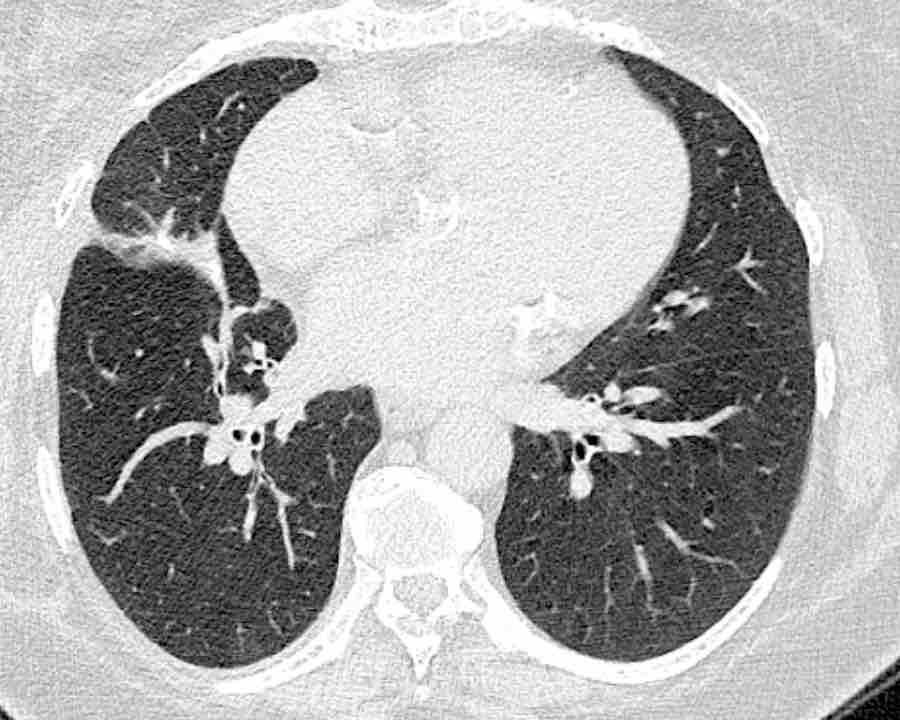

Các phân thùy phổi trên CT

Cuộn qua các hình ảnh để quan sát cách phổi được phân chia thành các phân thùy.